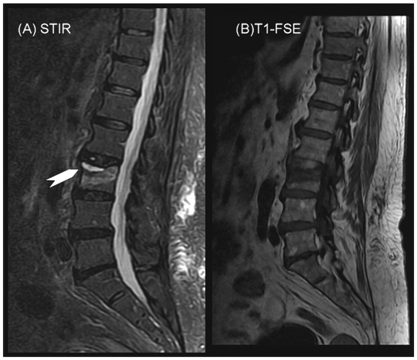

The fluid sign which is defined as a focal, linear, or triangular area of strong hyperintensity on STIR images on a background of diffuse hyperintensity in the vertebral body [Figure 4] because of acute collapse may be regarded as an additional morphologic feature that supports the benign osteoporotic nature of an acute vertebral fracture. Although this finding is significant, a tumor cannot be excluded because of this sign only.9

Figure 4 STIR sequence showing linear bright signal at the upper end plate of L3 (fluid sign) with a back ground of mild hyper-intensity.

Figure 4B T1WI showing hypo-intensity parallel to the upper end plate of L3.

The fluid sign at MR imaging may be regarded as an additional morphologic feature that supports the benign osteoporotic nature of an acute fracture. Although this finding is significant, a tumor cannot be excluded because of this sign. Other morphologic features or diffusion-weighted imaging should be considered if the diagnostic decision is difficult.

The fluid sign at MR imaging may be regarded as an additional morphologic feature that supports the benign osteoporotic nature of an acute fracture. Although this finding is significant, a tumor cannot be excluded because of this sign. Other morphologic features or diffusion-weighted imaging should be considered if the diagnostic decision is difficult.

Ragab et al.7 observed that fluid sign was more frequently present among patients with osteoporotic collapse (13/20) compared to those with neoplastic wedging (2/20). The findings of Ragab et al.7 are consistent with and extend those observed by Baur et al.9 who evaluated the occurrence, location and shape of the fluid sign in acute osteoporotic and neoplastic vertebral compression fractures at magnetic resonance (MR) imaging in 87 consecutive patients with acute vertebral compression fractures due to osteoporotic (N= 52) or neoplastic (N= 35) infiltration. They found that the fluid sign was significantly associated with osteoporotic fractures (P < 0.001). They concluded that the fluid sign is featured in acute vertebral wedge fractures that show bone marrow edema (BME). It can be an additional sign of osteoporosis and rarely occurs in metastatic fractures.